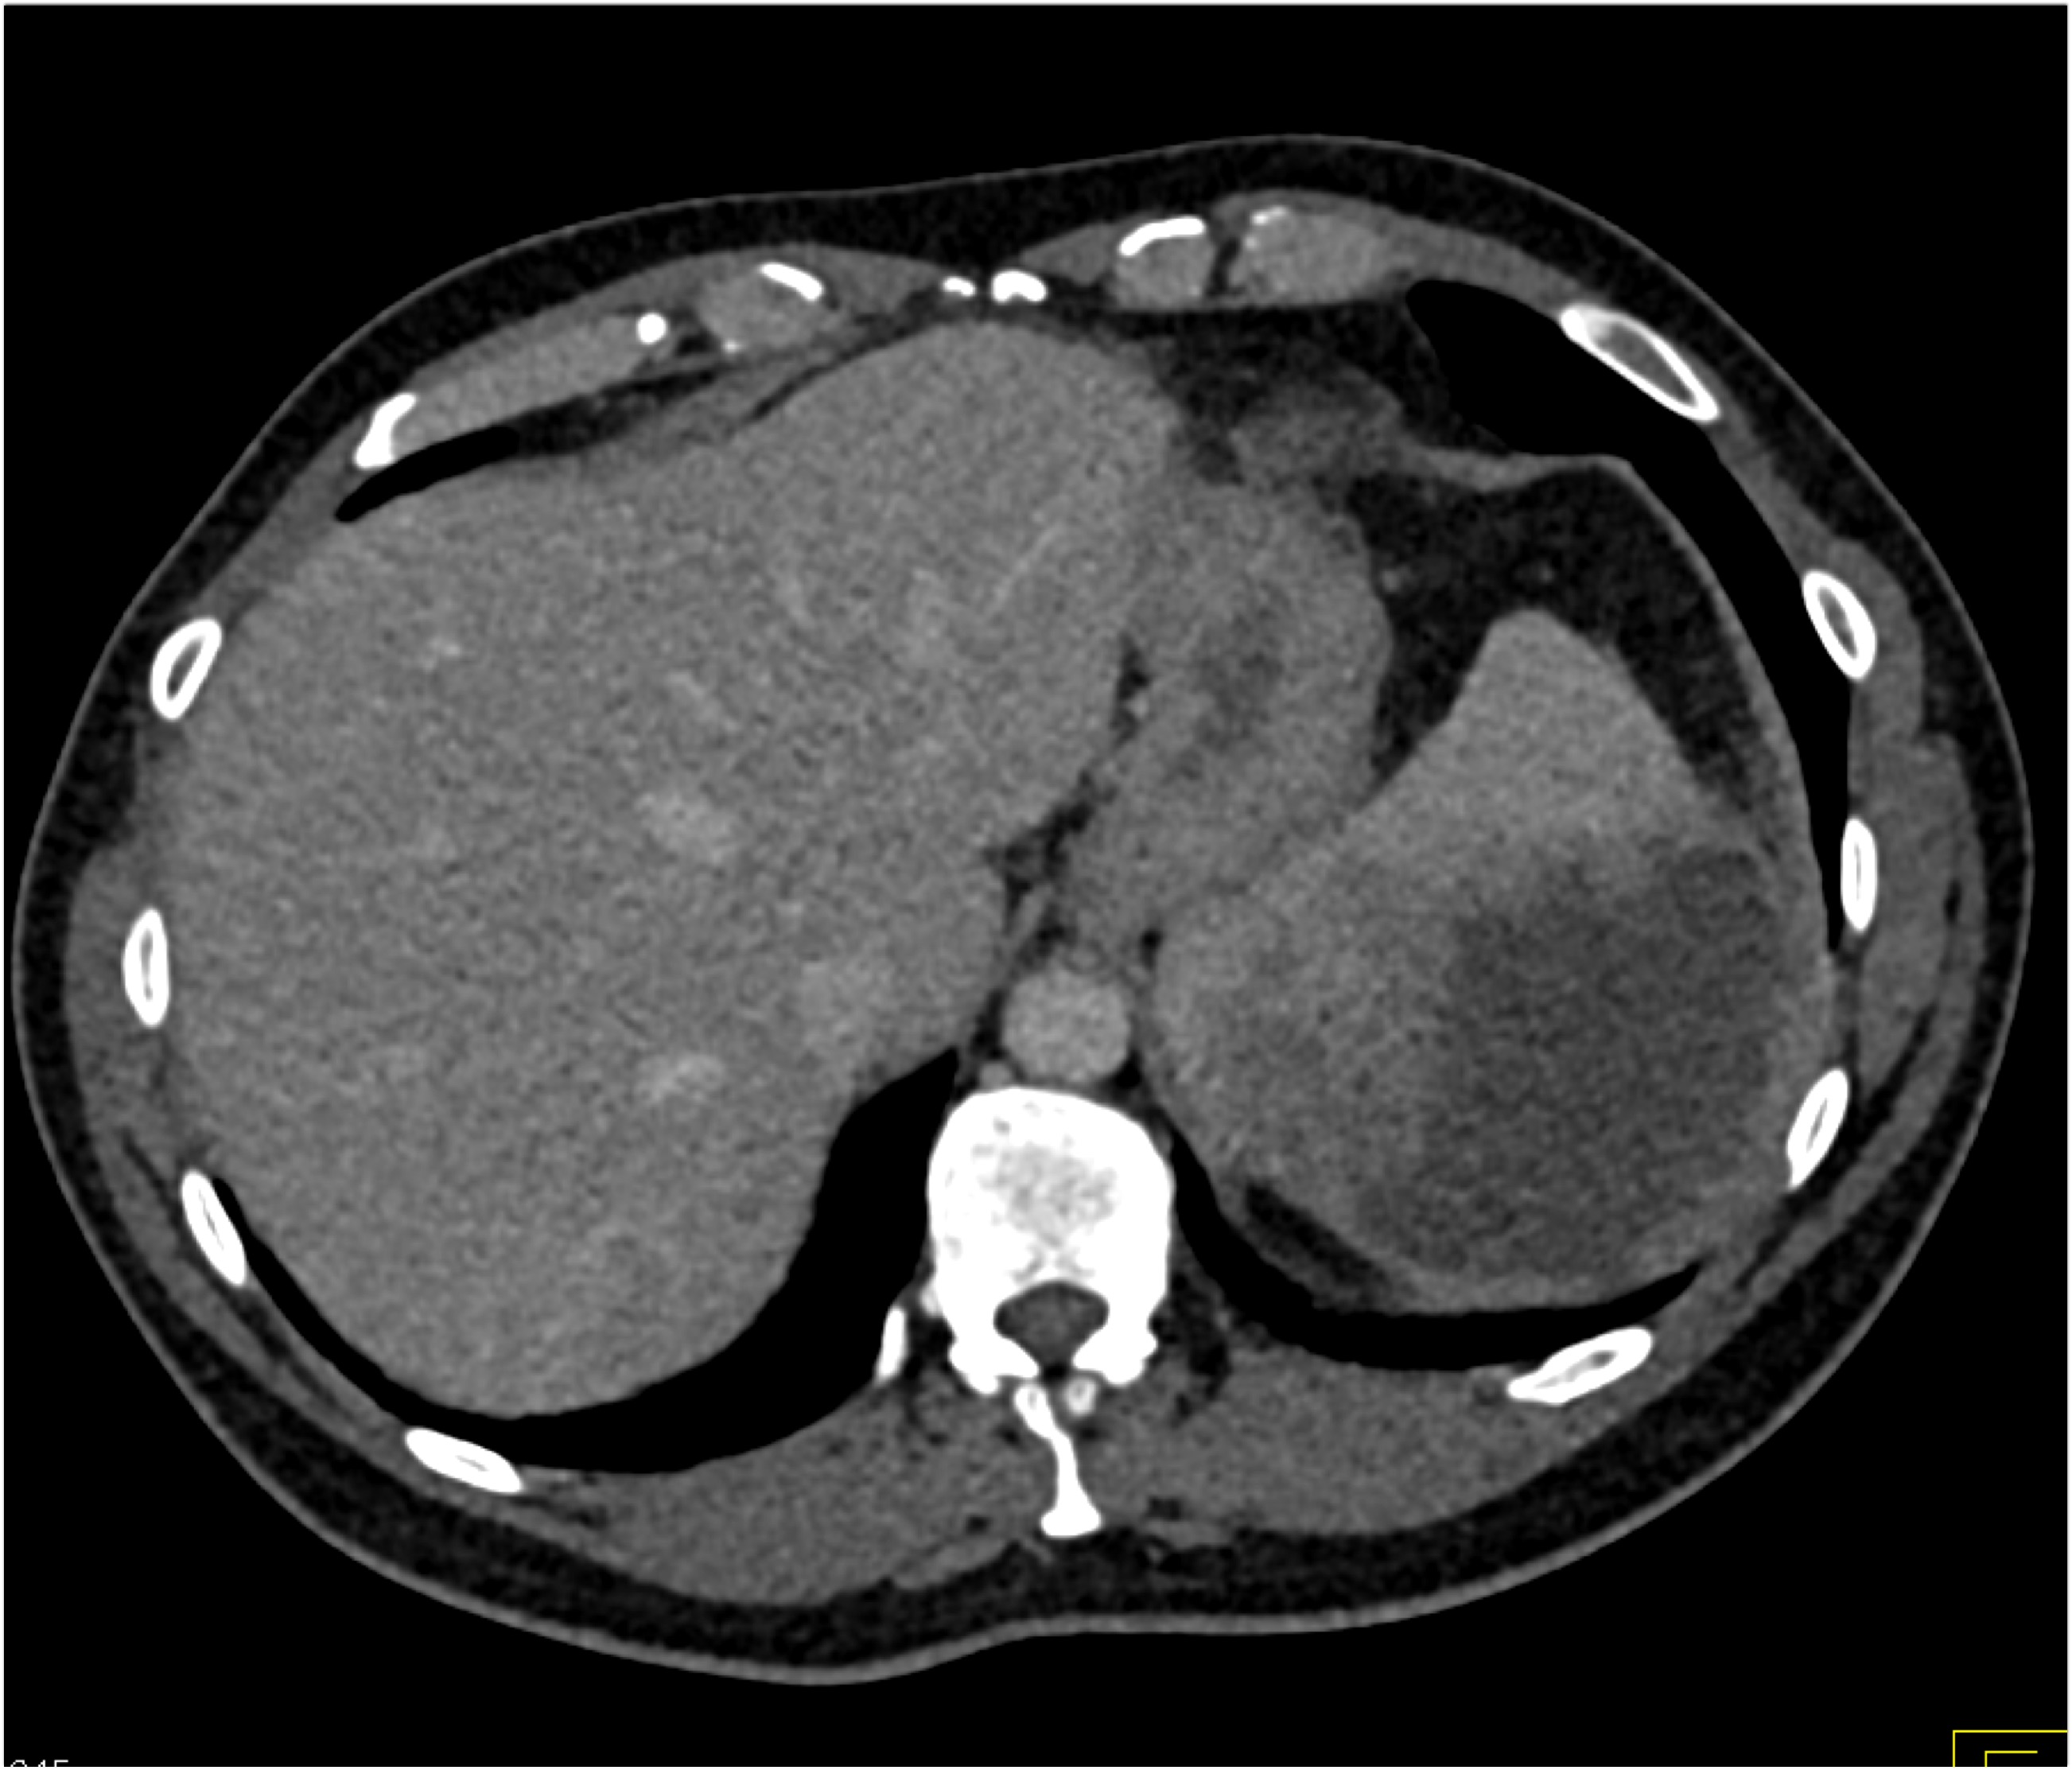

8) In this patient with RUQ pain and no history of trauma the best diagnosis is?

multiple hemangiomas

focal nodular hyperplasia

hepatic adenomas

angiosarcoma of the liver